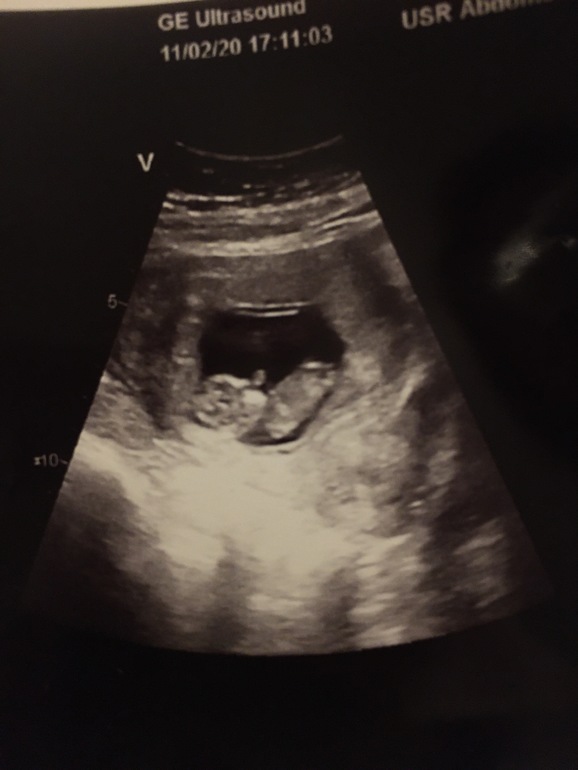

УЗИ 10-11 недель

Мне вчера не увидели, 11,5

А вы уже скрининг делали или просто УЗИ?

Скрининг. С 11 по 13 неделю у нас проводится.

Я просто УЗИ делала,скрининг в 12 недель